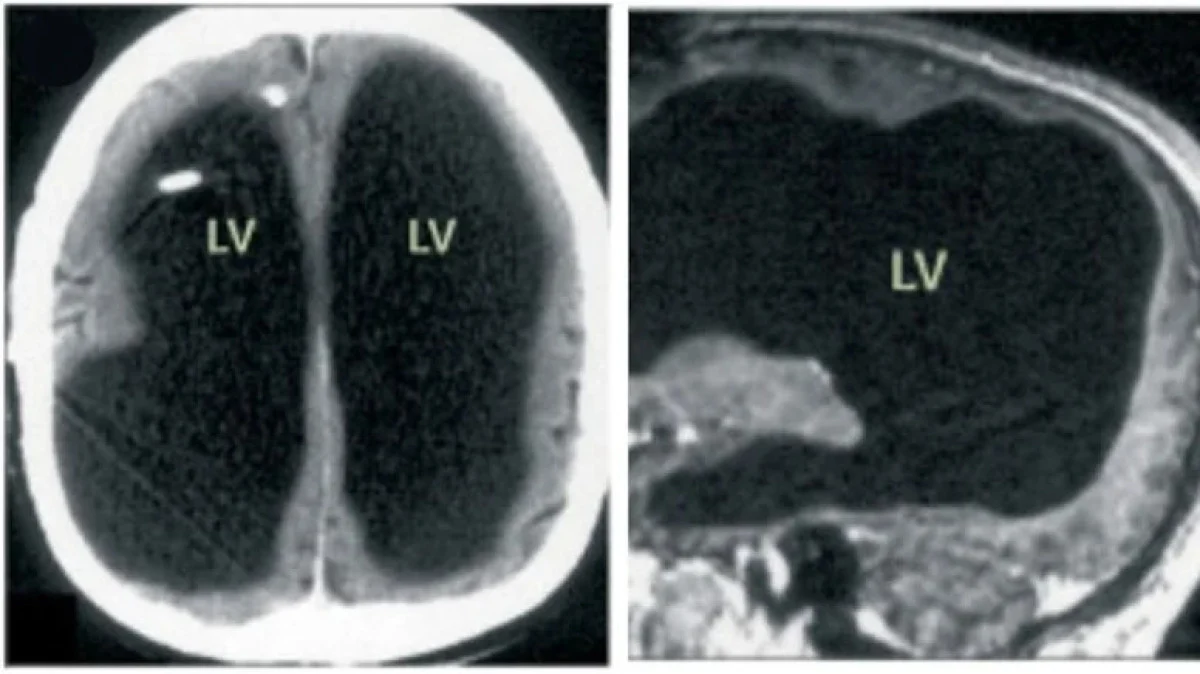

Yapılan tarama sonucunda, kafatasının büyük bir bölümünde sadece ince bir beyin dokusu tabakası olduğu ve "Hidrosefali" adı verilen bir durumun bulunduğu belirlendi.

Beyin taraması, adamın beyninin büyük bir kısmının eksik olduğunu görüldü. Tıbbi değerlendirmelerde, hastanın yaşamını normal bir şekilde sürdürdüğü, ailesinin olduğu ve çalışmaya devam ettiği tespit edildi.

Doktorlar, hastalığın nedeninin beyninde uzun yıllar boyunca biriken sıvı olduğunu düşünüyor. Hidrosefali nedeniyle beyin dokusunun zaman içinde tahrip olduğu ve sürecin yaklaşık 30 yıl boyunca sürdüğü tahmin ediliyor. Yapılan IQ testinde, hastanın zeka puanı 84 olarak belirlendi.